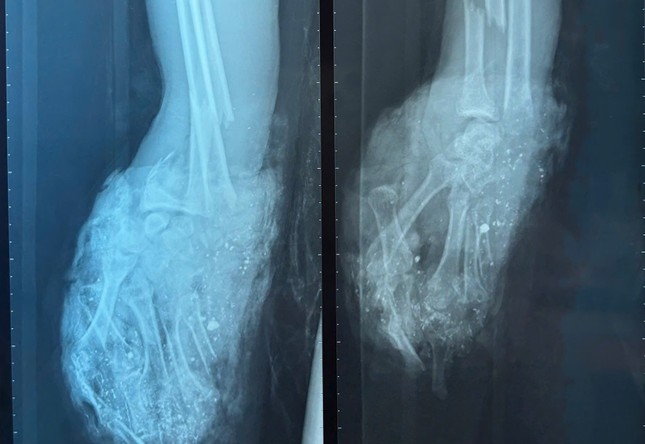

Bàn tay phải của bệnh nhân dập nát không còn khả năng điều trị bảo tồn

Trước đó bệnh nhân đã chơi pháo tự chế và bị phát nổ khi đang cầm trên tay. Qua thăm khám và kiểm tra hình ảnh, bác sĩ ghi nhận, bệnh nhân có vết thương phức tạp dập nát bàn tay phải, gãy hở đốt gần ngón I, vết thương ngón II, III, IV bàn tay trái.

Ngay sau khi tiếp nhận bệnh nhân, các bác sĩ đã hội chẩn nhanh và chỉ định thực hiện cuộc phẫu thuật cấp cứu. Bàn tay phải của bệnh nhân bị dập nát phức tạp, không còn khả năng điều trị bảo tồn nên ê kíp bác sĩ đã buộc phải đoạn chi và đóng mỏm cụt ở cổ tay. Bàn tay trái được cắt lọc hoại tử, cố định xương bị gãy, kết hợp xương đốt gần tay cái.